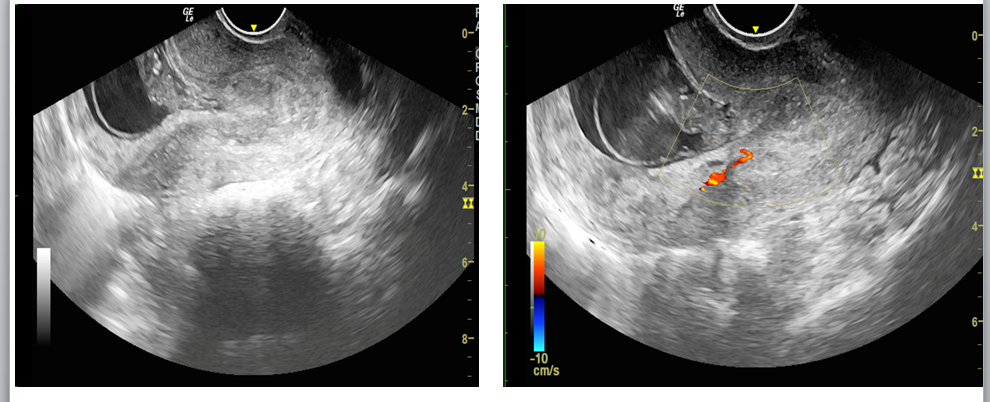

We report a case of a 24-year-old lady who was unable to conceive for a period of 8 years. Infertility workup was negative. In 2018, she conceived, however cardiac activity was not demonstrated in the fetus and eventually medical abortion was performed. Transvaginal sonography was performed for the same at a private center which did not pick up any uterine structural abnormality. In 2021, the patient presented to our emergency department with a 14-week gestation pregnancy with complaints of bleeding per vaginum for 2 days. Antenatal transvaginal ultrasound was performed for confirmation and viability of an intrauterine pregnancy. An intrauterine gestational sac with crown rump length corresponding to 8 weeks 5 days and absent cardiac activity was seen suggesting the diagnosis of missed abortion (Figure 1). Surrounding the gestational sac was fluid with internal echoes suggesting failure of implantation (Figure 2). A well-defined uniformly echogenic pedunculated lesion was seen in the endometrial cavity (Figure 3). As it was traced towards the point of its origin, a focally hypoechoic region was demonstrated interrupting the hyperechoic endometrial lining (Figure 4), classically described as the ‘interrupted mucosa sign’ [2]. On colour doppler image, a single vascular pedicle was demonstrated (Figure 5), known as the ‘pedicle artery sign’ [3]. Based on these classical features the diagnosis of an endometrial polyp was made. It was seen to abut the gestational sac suggesting mechanical hindrance to growth of the embryo (Figure 6). On real time imaging, the endometrial polyp was seen prolapsing from towards the uterine fundus to the lower uterine segment (Figure 7). For better characterization of the endometrial polyp, it has been recommended to distend the uterine cavity with saline (also known as saline infusion sonohysterography) [4,5], however in our case it was unwarranted because the gestational sac and fluid naturally distended the uterine cavity and helped in optimum visualization (Figure 4,6). Figure 8 depicts another case of an endometrial polyp showing a non-gravid uterus with an echogenic lesion in the endometrial cavity showing the classical interrupted mucosa sign (Figure 8A) and the feeding artery sign (Figure 8B).

Figure 2. Transvaginal sonography shows a gestational sac within the endometrial cavity without a definite site of implantation. Note the surrounding echogenic fluid.

Figure 5: Color doppler images show a single feeding artery supplying the stalk of polyp, described as ‘pedicle artery sign’.

Figure 8: Another case of endometrial polyp showing a non-gravid uterus with an echogenic lesion in the endometrial cavity showing the classical interrupted mucosa sign (Figure 8A, red arrow) and feeding artery sign (Figure 8B, green arrow).